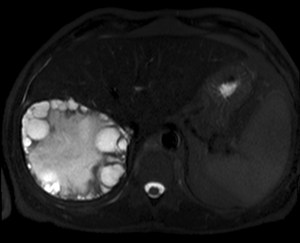

Al llegar al compartimento 6 me encuentro un tendón engrosado de tamaño y aspecto heterogéneo típico de afectación por tendinosis, con líquido en la vaina, te lo señala la imagen con flecha amarilla. Lo recorro y confirmo los hallazgos eje corto y eje largo, hago medidas y compruebo el doppler que marca Neovascularización asociada.

Observa las tres imágenes superiores, son muy ilustrativas, son comparativas de normalidad hallazgos patológicos, el izquierdo claramente patológico y el derecho claramente normal.